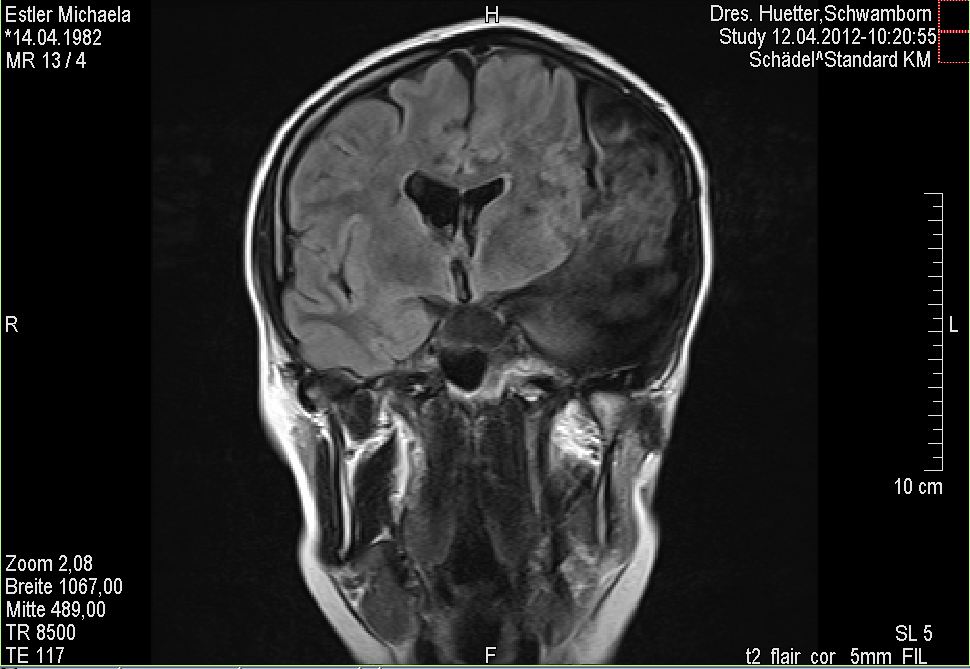

Wenn ich jetzt so zurück blicke auf diesen Moment, bzw. die erste Zeit danach, muss ich mir eingestehen, dass mein Bauchgefühl mir schon damals sagte, dass es für mich an der Zeit ist, wieder mehr zu mir selbst zu finden, bzw. mein Leben wieder mehr als Geschenk an zu sehen und nicht als Selbstverständlichkeit. Als ich aus dem Krankenhaus entlassen wurde, war damals noch die Prognose, dass ich in ca. drei Monaten wieder zurück in mein „altes“ Leben könne. Mit meiner Arbeit, meinem Alltag, usw. Das war für mich ein ausgegebenes Ziel, quasi zu Beginn 2009 wieder völlig die alte Michaela zu sein. Als ich bei der ersten größeren Nachuntersuchung war, im Dezember 2008 zeigten die gemachten MRT Bilder nicht das gewünschte Ergebnis. Ich weiß noch, dass ich zuerst dachte, der Arzt hätte MRT Bilder von vor meiner OP auf dem Bildschirm. Ich glaube mein Dad, der mich damals begleitete, dachte dasselbe. Der Arzt eröffnete mir wenig später dann allerdings, dass es die aktuellen Bilder wären und er mir leider mitteilen müsste, dass durch die OP nicht das erreicht wurde, was man eigentlich dachte erreichen zu können und dass er mir quasi offen und ehrlich mitteilen müsse, dass die Operation umsonst gewesen sei. Es zog mir den Boden unter den Füßen weg. Ich konnte nicht verstehen, wie all diese vielen und großen Aufwendungen nichts gebracht haben sollen. Und ja, ich war sauer. Aber nicht auf den Arzt, nein! Den schätzte ich sehr für seine Offenheit und Ehrlichkeit. Selten hatte ich bisher mit solch einem wirklich netten Menschen zu tun.

Damals setzte bei mir dieses Gefühl des Fallens ein. Mit so etwas hatte ich nicht gerechnet. In keinster Weise! Ich wurde fast schon ein bisschen panisch, denn ich hatte keinen Plan B. Es gab keinen Plan B. Das einzige was laut Arzt erst einmal gemacht werden konnte ist – WARTEN. Jaaaa klar. Weil ich ja bei so was gut bin. Die Tage und die Wochen verstrichen und weitere drei Monate später wieder MRT. Das Ergebnis erschütternd und niederschmetternd. Für mich war dann zu diesem Zeitpunkt zum ersten Mal klar, dass auch die Möglichkeit besteht, dass sich das gar nie nicht mehr ändern würde.